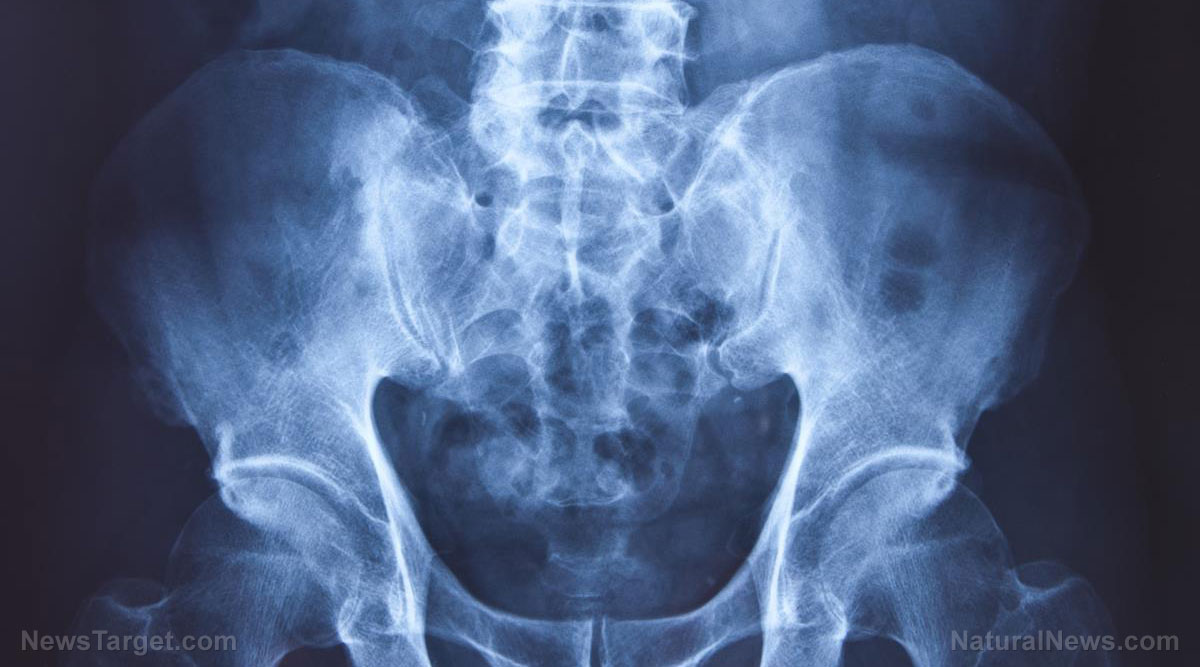

Increasing vitamin C intake can reduce hip fracture risk by 44 percent: Study

(Natural News) When it comes to healthy bones, people often look to calcium and vitamin D. However, experts suggest adding an unlikely vitamin to the mix: vitamin C. In a recent study published in Osteoporosis International, a team of researchers from Tufts University, Harvard Medical School and the Boston University School of Public Health revealed that taking vitamin C can...